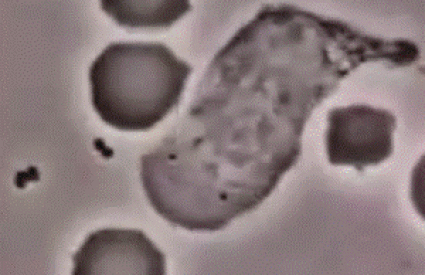

Lov na zlatni stafilokok, leukociti u akciji

Zahvaljujući YouTubeu i pokojnom profesoru medicine sa sveučilišta Vanderbilt Davidu Rogersu, danas imamo priliku svojim očima uvjeriti se u fantastičnost našeg imunološkog sustava. Naime, na videu koji datira iz 50-ih godina prošloga stoljeća prikazan je lov na bakteriju zlatni stafilokok (Staphylococcus aureus).

Neutrofili su leukociti (bijela krvna zrnca) koji štite organizam od bakterijske ili gljivične infekcije kao i drugih sitnih izazivača upalnih procesa. Oni uglavnom predstavljaju prvi odgovor organizma na infekcije.

U videu stafilokok se vidi kao malena crna flekica dok su crvena krvna zrnca velike okrugle mase. Neutrofili su providne mase koje se kreću u međuprostoru i love bakterije.